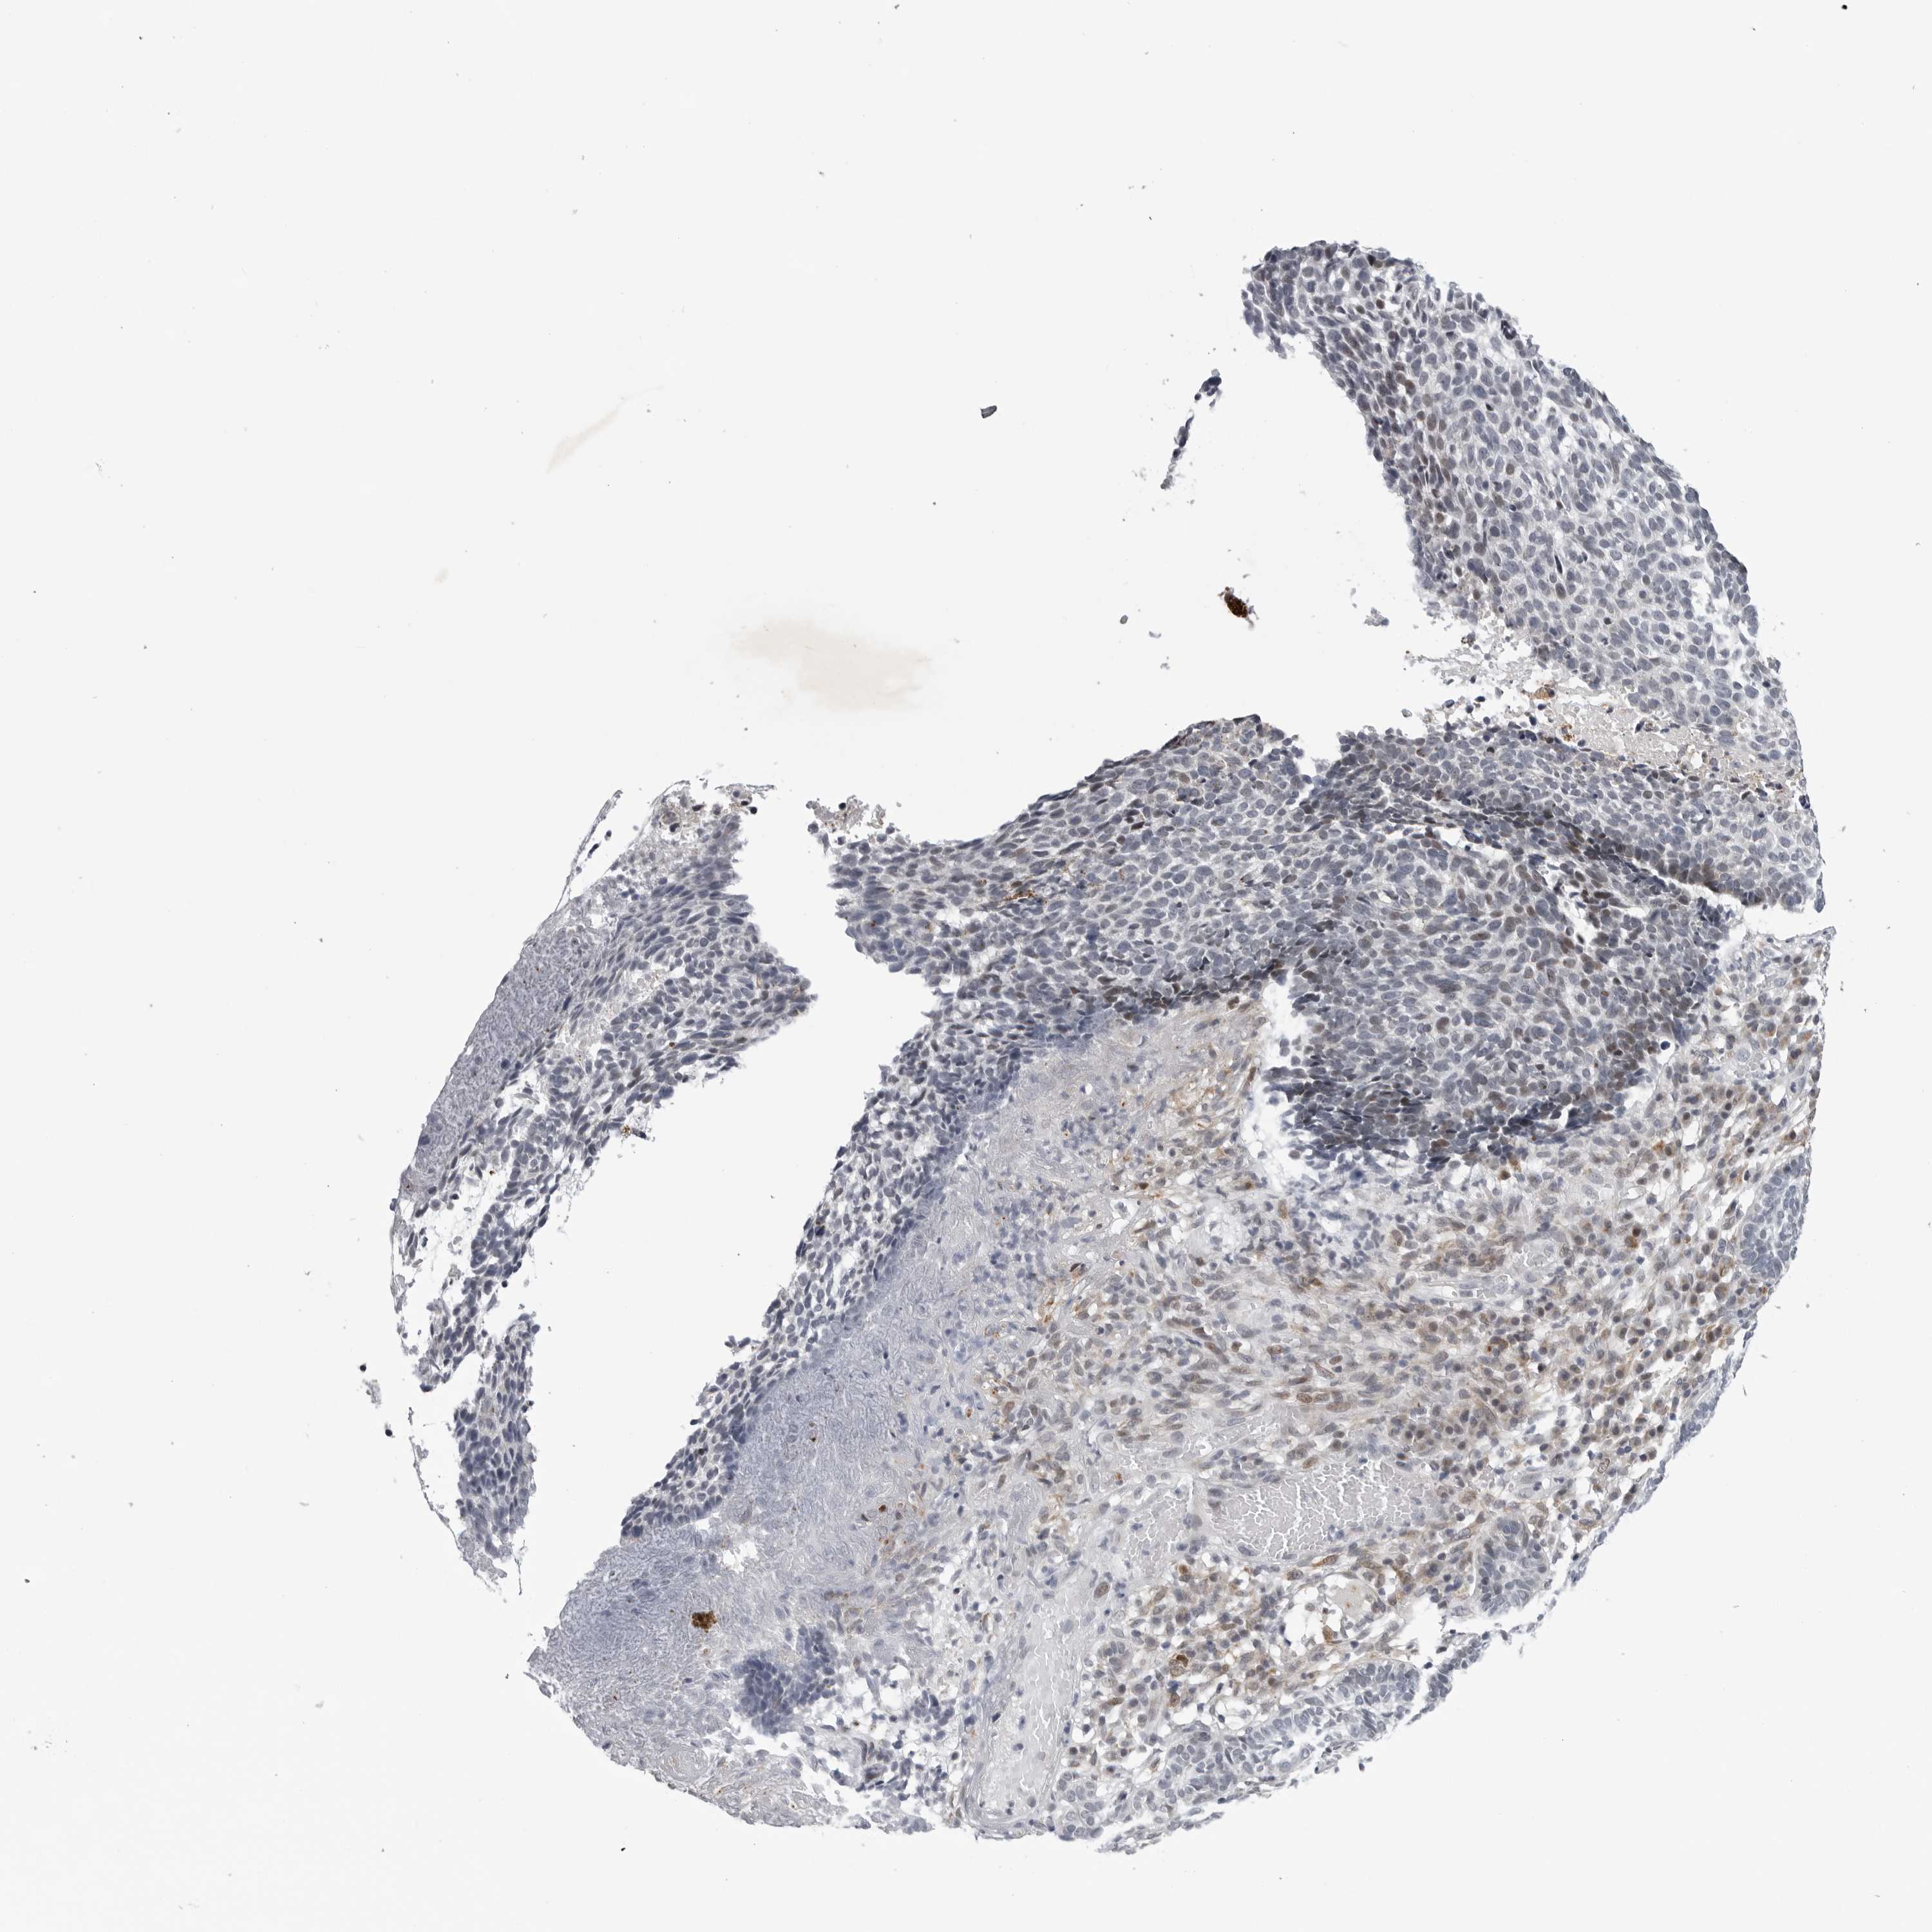

SKIN CANCER - Protein expressioni

A mouse-over function shows sample information and annotation data. Click on an image to view it in a full screen mode. Samples can be filtered based on level of antibody staining by selecting one or several of the following categories: high, medium, low and not detected. The assay and annotation is described here.

Each image is clickable and will lead to virtual microscopy that enables deeper exploration of all samples and also displays staining intensity scores, fraction scores and subcellular localization as well as patient and tissue information for each sample.

Antibody HPA027401

Squamous cell carcinoma, metastatic, NOS